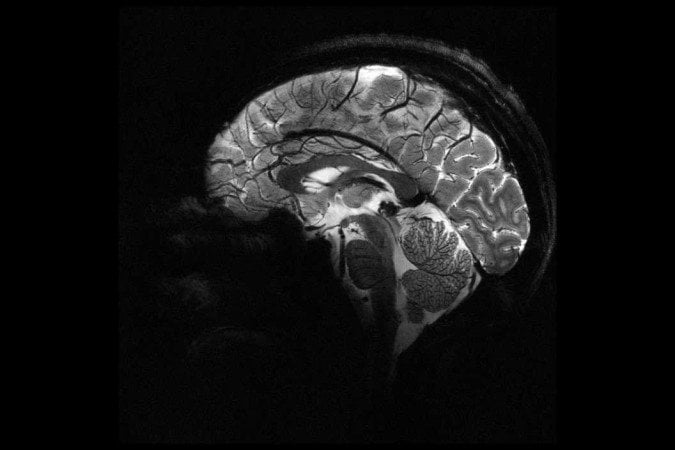

Prepare-se para ser surpreendido! Recentemente, a Comissão Francesa de Energia Atômica e Energia Alternativa (CEA) revelou à imprensa o que seriam as primeiras imagens de um cérebro humano. As mesmas foram capturadas por um scanner de ressonância magnética (RM) de 11,7 Teslas, o mais potente do mundo, lançando luz sobre a anatomia e função do órgão.

Vale destacar que esta máquina pode captar imagens com resolução 10 vezes maior do que os scanners de ressonância tradicionais, chegando a registar microscópicos do cérebro humano em apenas 4 minutos, ou minúsculos vasos sanguíneos que irrigam o córtex cerebral. O nível de precisão é sem precedentes! Impressionante, não?

Com auxílio de máquinas de ressonância como Iseult, os médicos poderão identificar mais facilmente em seus pacientes as causas de doenças neurodegenerativas, como Alzheimer e Parkinson, transtornos psicológicos, incluindo depressão e esquizofrenia, e até mesmo o desenvolvimento cerebral em crianças. Também mapear a distribuição de substâncias químicas vitais, como o lítio, em tratamentos para transtorno bipolar. Isso levaria a diagnósticos precoces e tratamentos mais eficazes.

Por hora, os desenvolvedores do scanner de ressonância Iseult afirmam que a máquina ainda não está pronta para uso clínico direto. Mas, quando isso for possível, veremos avanços significativos nos métodos de diagnóstico e tratamentos hospitalares. Será uma nova era para a exploração do cérebro humano.